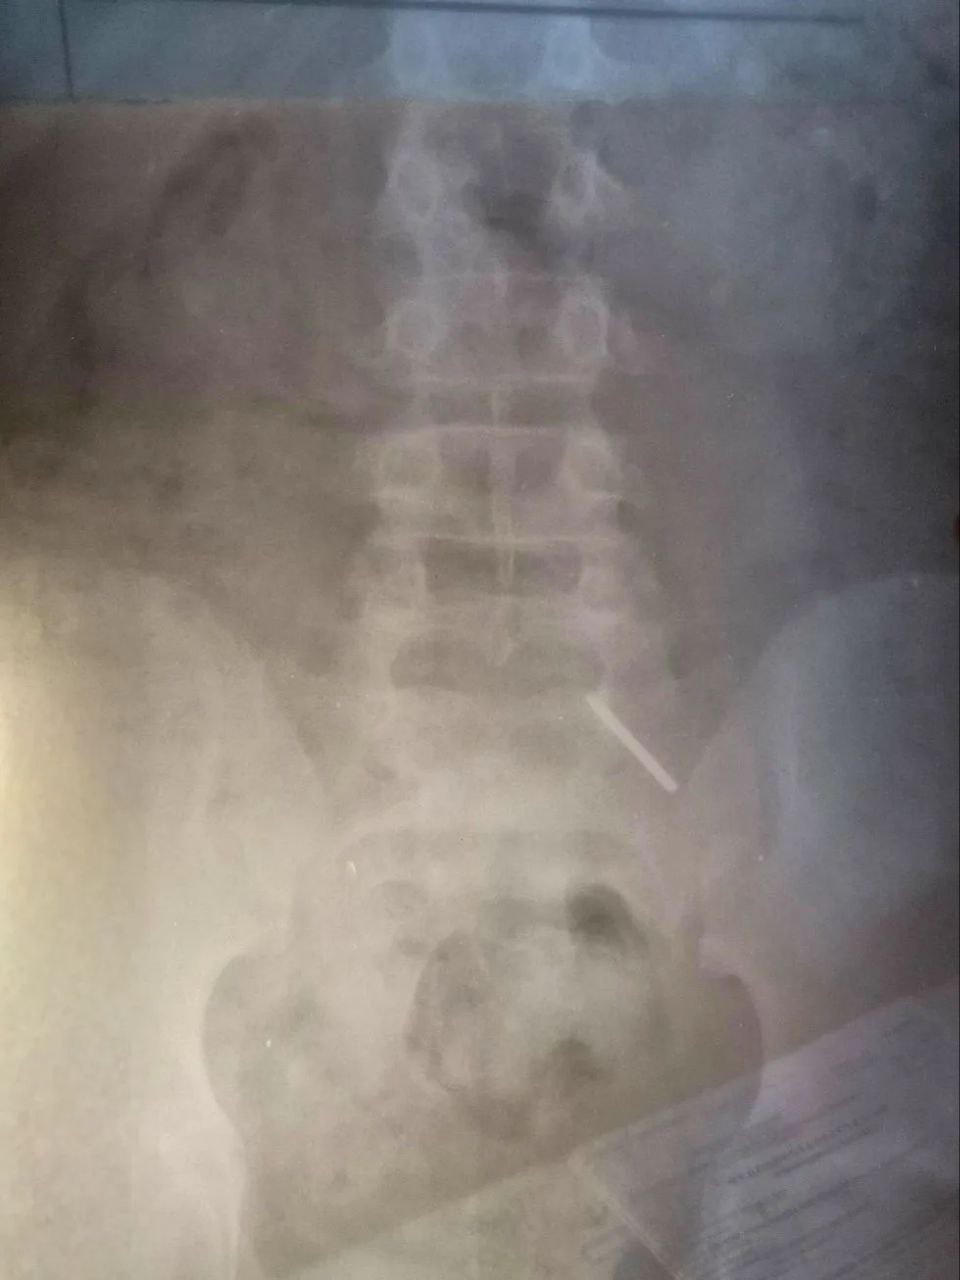

Как рассказала детский хирург Дарья Гусева, из-за позднего обращения за помощью достать предмет с помощью эндоскопа не удалось. Основной задачей врачей стало предотвратить повреждение кишечника и внутреннее кровотечение. Ребенка тщательно наблюдали, делали контрольные рентгеновские снимки.